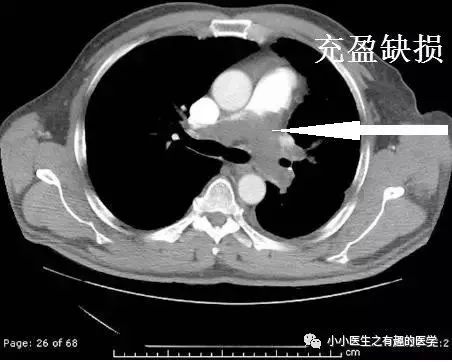

曾经,一看到肺动脉血管成像(CTA)上有充盈缺损,就大呼:肺栓塞了,肺上长血栓了!立马抗凝、对症治疗。

后来发现,肺动脉造影才是金标准。我就纳闷:肺动脉CTA上发现了充盈缺损,那不是血栓会是神马?

这是什么?妥妥的肺栓塞啊,还能有啥?

这么大一个血栓!

充盈缺损的地方,密度不均匀,并且有强化,血栓里面没有血管,一般不会强化,所以有可能是肿瘤。